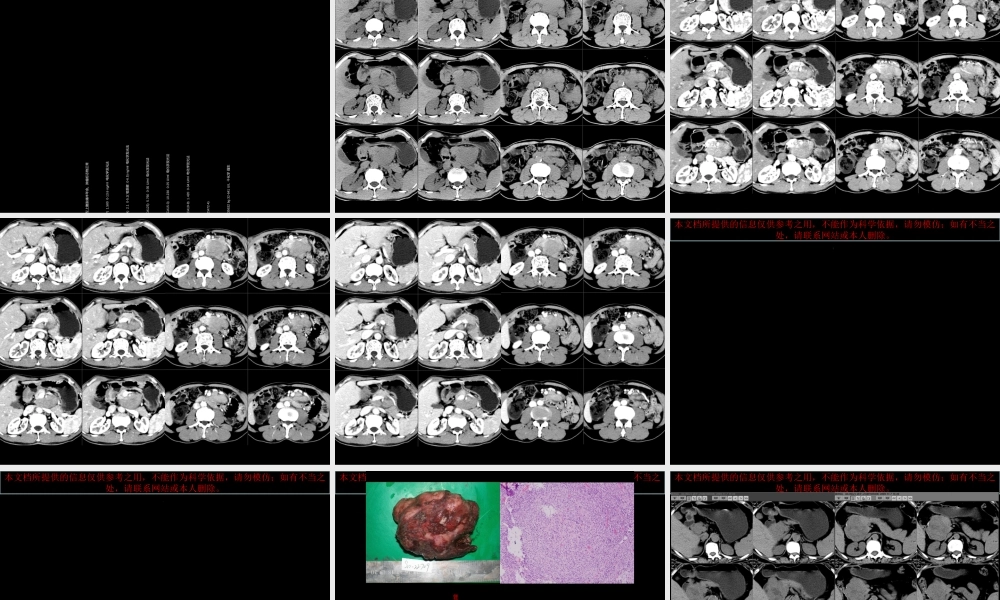

本文档所提供的信息仅供参考之用,不能作为科学依据,请勿模仿;如有不当之处,请联系网站或本人删除。本文档所提供的信息仅供参考之用,不能作为科学依据,请勿模仿;如有不当之处,请联系网站或本人删除。本文档所提供的信息仅供参考之用,不能作为科学依据,请勿模仿;如有不当之处,请联系网站或本人删除。本文档所提供的信息仅供参考之用,不能作为科学依据,请勿模仿;如有不当之处,请联系网站或本人删除。本文档所提供的信息仅供参考之用,不能作为科学依据,请勿模仿;如有不当之处,请联系网站或本人删除。病例 2本文档所提供的信息仅供参考之用,不能作为科学依据,请勿模仿;如有不当之处,请联系网站或本人删除。本文档所提供的信息仅供参考之用,不能作为科学依据,请勿模仿;如有不当之处,请联系网站或本人删除。本文档所提供的信息仅供参考之用,不能作为科学依据,请勿模仿;如有不当之处,请联系网站或本人删除。本文档所提供的信息仅供参考之用,不能作为科学依据,请勿模仿;如有不当之处,请联系网站或本人删除。病例 3本文档所提供的信息仅供参考之用,不能作为科学依据,请勿模仿;如有不当之处,请联系网站或本人删除。本文档所提供的信息仅供参考之用,不能作为科学依据,请勿模仿;如有不当之处,请联系网站或本人删除。本文档所提供的信息仅供参考之用,不能作为科学依据,请勿模仿;如有不当之处,请联系网站或本人删除。本文档所提供的信息仅供参考之用,不能作为科学依据,请勿模仿;如有不当之处,请联系网站或本人删除。Castleman 病CT 表现小讲座 福建医科大学附属第一医院影像科孙辉红( sunhvhong@sina.com )本文档所提供的信息仅供参考之用,不能作为科学依据,请勿模仿;如有不当之处,请联系网站或本人删除。病例 1•男, 58 岁,反复左上腹胀痛半年余。肿瘤标志物正常•*1 甲胎蛋白 (AFP) 1.580 0-13.6 ng/ml 电化学发光法 •*2 癌胚抗原 (CEA) 2.1 0-5.2( 吸烟者 :0-6.5) ng/ml 电化学发光法 •3 糖类抗原 125(CA125) 5.760 0-35 U/ml 电化学发光法 •4 糖类抗原 15-3(CA15-3) 10.230 0-25 U/ml 电化学发光法 •5 糖类抗原 19-9(CA19-9) 1.420 0-34 U/ml 电化学发光法 •6 糖类抗原 72-4(CA72-4) •淀粉酶 (AMYL) >35632 bg 32-641 U/L 干化学 强生 本文档所提供的信息仅供参考之用,不能作为科学依据,请勿模仿;如有不当之处,请...